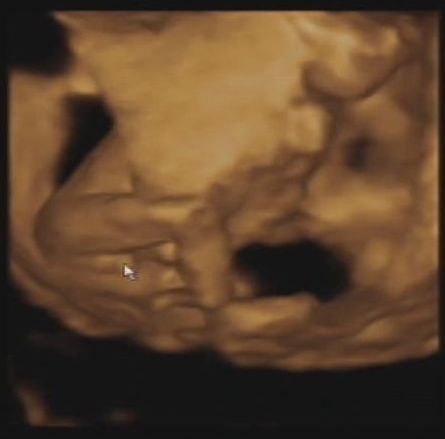

18+6

kuki

Ki is van odabent